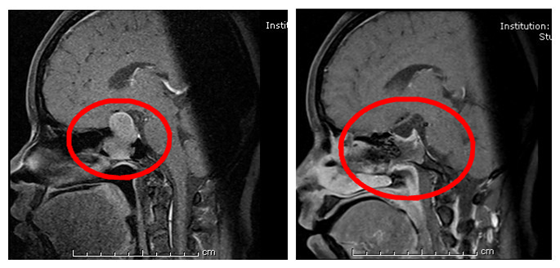

3月5日,袁贤瑞主任团队在进行充分的术前讨论后,为陆女士采取了“经鼻碟路入内镜下垂体瘤切除术”,手术过程十分顺利,肿瘤全切除。

患者术前术后MRI对比图

据悉,垂体瘤是一种导致神经内分泌功能异常的颅内肿瘤。患者出现视力减退,视野缺损,激素分泌异常,女患者常出现月经失调,肢端粗大等男性体征。经鼻蝶入路内镜下垂体瘤切除术是目前湘雅常德医院已经在开展的一种微创手术,可以用鼻内镜经鼻腔切除垂体瘤,避免了开颅手术,给患者减轻了很多痛苦,也给一些爱美的女士保留了一头美丽的秀发,手术创伤小,恢复也很快。